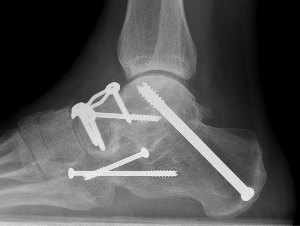

Fixation

- TJN screws

- CCJ screws +/- plate

- STJ screws